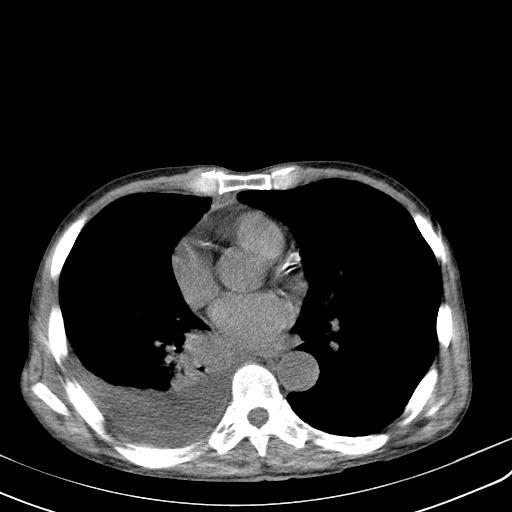

男性 75  咳嗽 一周前发热最高达39

右肺继发型tb并右侧tb性胸腔炎,右侧胸腔大量积液并右下肺膨胀不全,慢支肺气肿、多发肺大泡。建议抽胸水实验室检查并复查排除恶性在占位。

右上肺继发型肺结核,右胸腔中等量积液。

左上肺大泡。

结核的基础上有纵隔淋巴结肿大,右侧有胸水,但右侧纵隔反而窄,说明有肺有不张。

再就是右下肺有块影,和不张混合,还是不能除外肺癌。

补充材料,患者2月份ct片大致正常,双侧胸腔积液,2月份抽胸水未发现ca细胞,现患者发热,痰多,各气管通畅,

1)右肺继发型肺结核。2)左肺胸膜下多发性肺大泡。3)右侧胸腔积液。